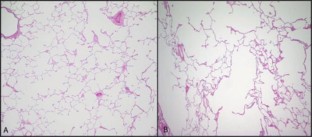

Alpha-1 antitrypsin deficiency (AATD) is an inherited disorder characterized by low serum levels of alpha-1 antitrypsin (AAT). Loss of AAT disrupts the protease–antiprotease balance in the lungs, allowing proteases, specifically neutrophil elastase, to act uninhibited and destroy lung matrix and alveolar structures. Destruction of these lung structures classically leads to an increased risk of developing emphysema and chronic obstructive pulmonary disease (COPD), especially in individuals with a smoking history. It is estimated that 3.4 million people worldwide have AATD. However, AATD is considered to be significantly underdiagnosed and underrecognized by clinicians. Contributing factors to the diagnostic delay of approximately 5.6 years are: inadequate awareness by healthcare providers, failure to implement recommendations from the American Thoracic Society/European Respiratory Society, and the belief that AATD testing is not warranted. Diagnosis can be attained using qualitative or quantitative laboratory testing. The only FDA approved treatment for AATD is augmentation therapy, although classically symptoms have been treated similarly to those of COPD. Future goals of AATD treatment are to use gene therapy using vector systems to produce therapeutic levels of AAT in the lungs without causing a systemic inflammatory response.

D'Armiento J, Dalal SS, Okada Y, Berg RA, Chada K (1992) Collagenase expression in the lungs of transgenic mice causes pulmonary emphysema. Cell 71(6):955–961